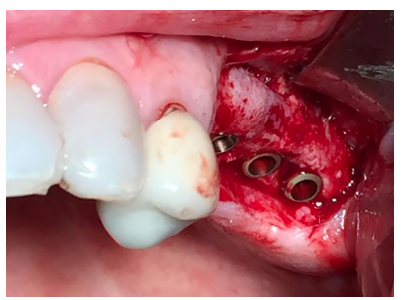

Se realizó una incisión lineal crestal con descarga distal para la obtención del campo quirúrgico. Se utilizó la técnica de fresado biológico a 100 rpm insertándose 3 implantes en posición 25, 26, 27 de 3,5 mm x 10mm (SIN Unitite®), con un torque de 50 N/cm obteniéndose una correcta estabilidad primaria (Figura 11). Tras la colocación de los tornillos de cierre, se procedió a la sutura del colgajo con Supramid® 4/0 aguja 3/8 (Figura 12).